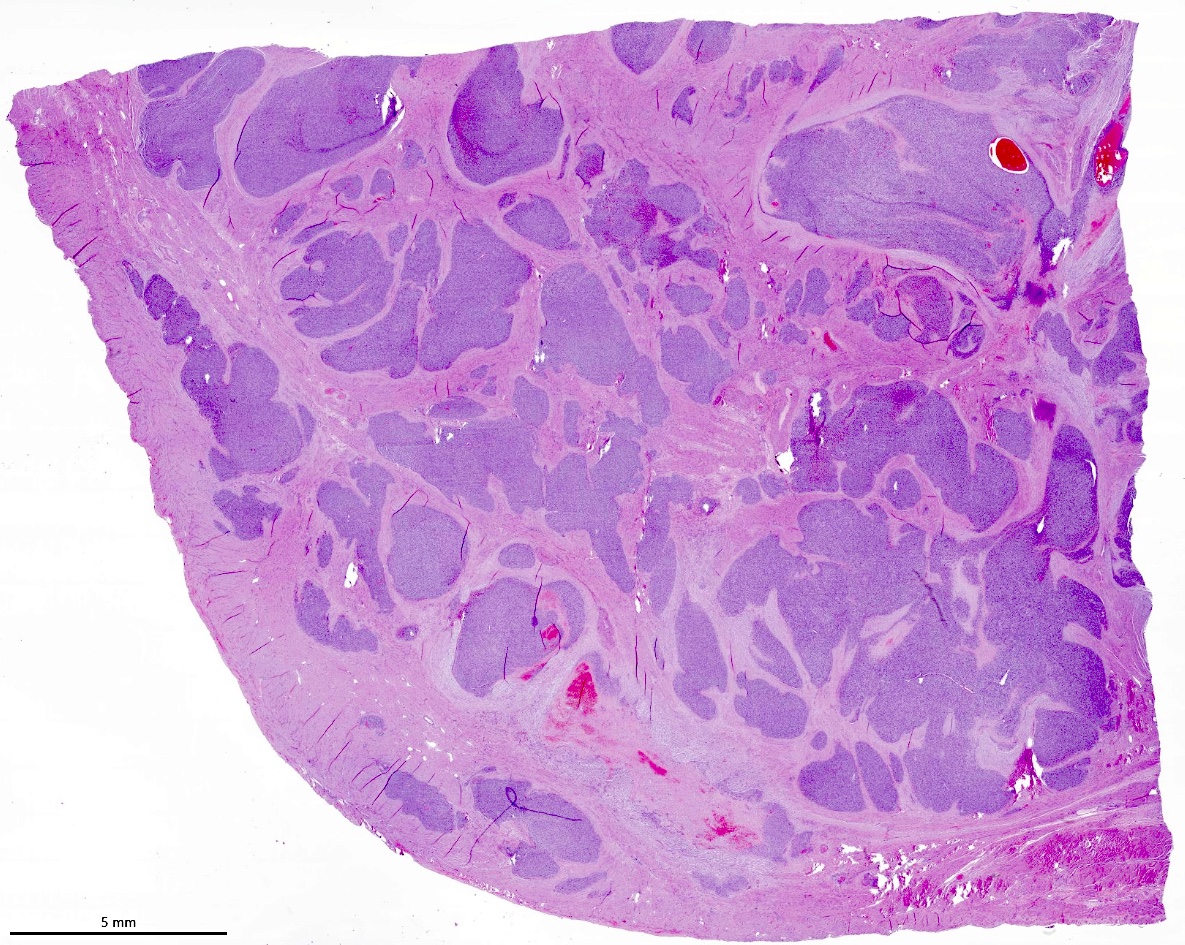

Microscopic (histologic) description

- Irregular cellular islands, forming permeative tongue-like pattern of myometrial invasion with frequent vascular invasion

- Monotonous oval to spindle cells with minimal cytologic atypia, vesicular chromatin and scant cytoplasm

- Mitotic count is usually low (< 5/10 high power fields), necrosis is usually absent

- Tumor cells may whorl around delicate arteriolar type vessels, reminiscent of proliferative phase endometrial stroma

- May have admixed collagen bands / plaques and foamy histiocytes

- May have smooth muscle differentiation, particularly in a starburst morphology, with collagen bands radiating towards the periphery of the nodule

- Other reported types of differentiation: fibromyxoid / fibrous, sex cord-like, epithelioid, rhabdoid, endometrioid glands, pseudopapillae, clear cells, bizarre cells, adipose tissue (Mod Pathol 2016;29:S92)

Microscopic (histologic) images

Contributed by Elizabeth Kertowidjojo, M.D., Ph.D., M.P.H. and Ayse Ayhan, M.D., Ph.D.

D. Low grade endometrial stromal sarcoma. The tumor shows a polypoid component, as well as a characteristic permeative tongue-like invasion pattern seen on low power. The presence of invasion rules out an endometrial stromal nodule (answer B) and cellular leiomyoma (answer A). The lack of any glandular component rules out endometrioid carcinoma (answer C). While low grade endometrial stromal sarcoma can have sex cord-like differentiation, the presence of conventional low grade endometrial stromal sarcoma rules out uterine tumor resembling ovarian sex cord tumor (answer E).